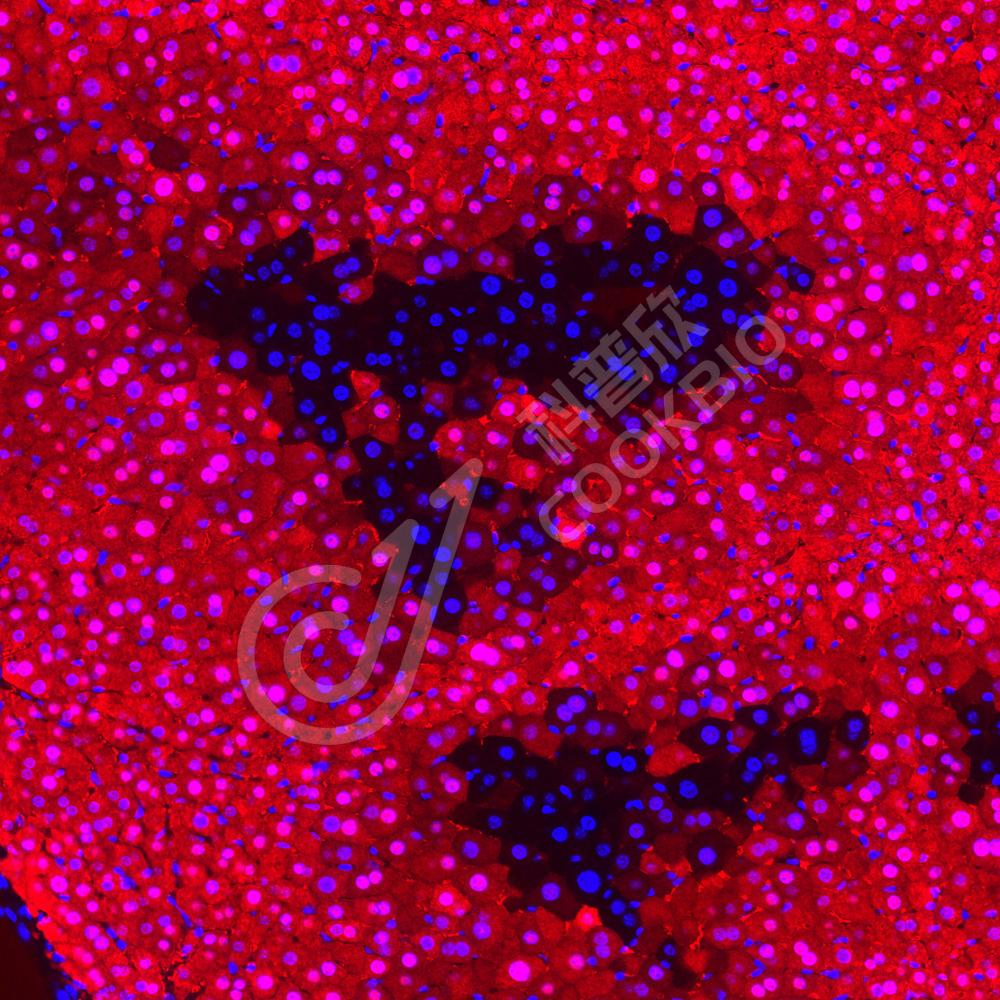

IHC检测Aspartate Aminotransferase蛋白(货号 K1340203).

样品: 大鼠脑, 4%多聚甲醛 (货号KSG1101) 固定12-24小时.

抗原修复: 柠檬酸抗原修复液(干粉, pH 6.0) (KSG1201), 98℃, 20分钟.

—抗: 1: 3000稀释, 4℃ 孵育过夜.

二抗: S-vision免疫组化多聚二抗(山羊抗兔),即用型 (货号KB3906), 室温孵育20分钟.